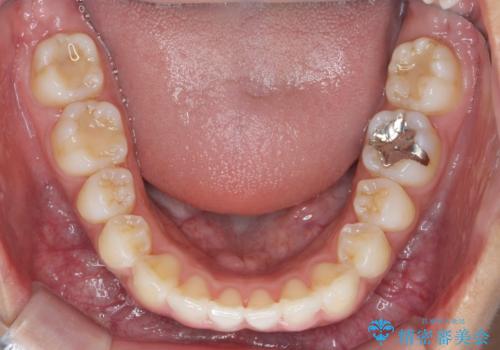

- 前歯のガタつき、突出感のある前歯の改善を求めて来院されました。

前歯の角度を改善し審美性を高めるとともに、奥歯のガタつきも並べ直すことで安定した咬合関係の確立を目指します。

歯列の側方拡大をしっかりと行ったことで歯を抜かずに前歯の角度をしっかりと改善することができました。